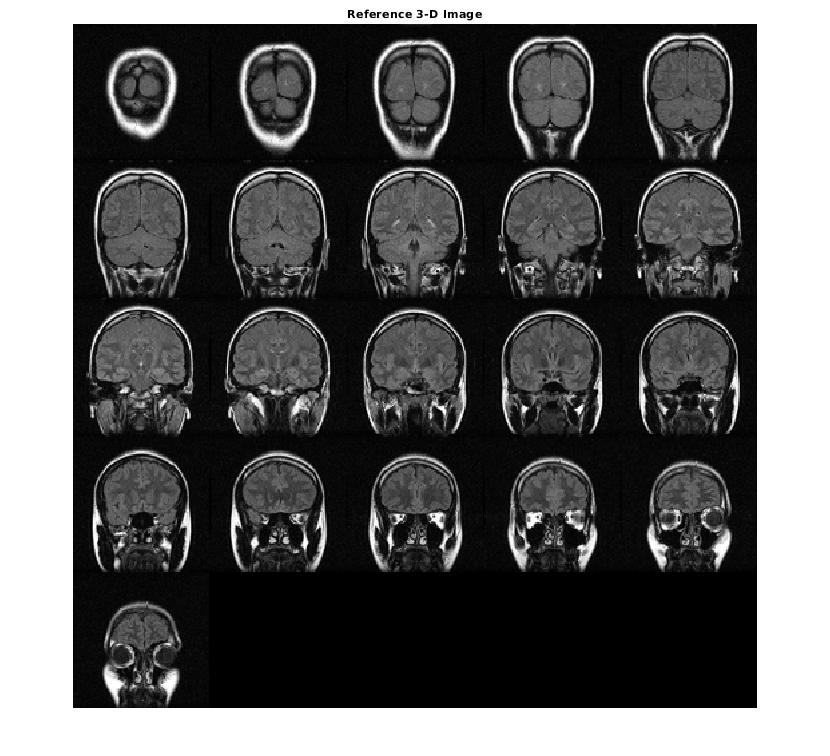

Измените ссылку как стек полутоновых срезов для отображения.

ref = reshape(mristack,[256,256,1,21]);

Отобразите ссылочный объем как срезы. Чтобы отобразиться правильно на экране, ссылочный объем уменьшается фактором 0,5 использований imresize.

ref_downsized = imresize(ref,0.5);

figure

montage(ref_downsized,'DisplayRange',[])

title('Reference 3-D Image')